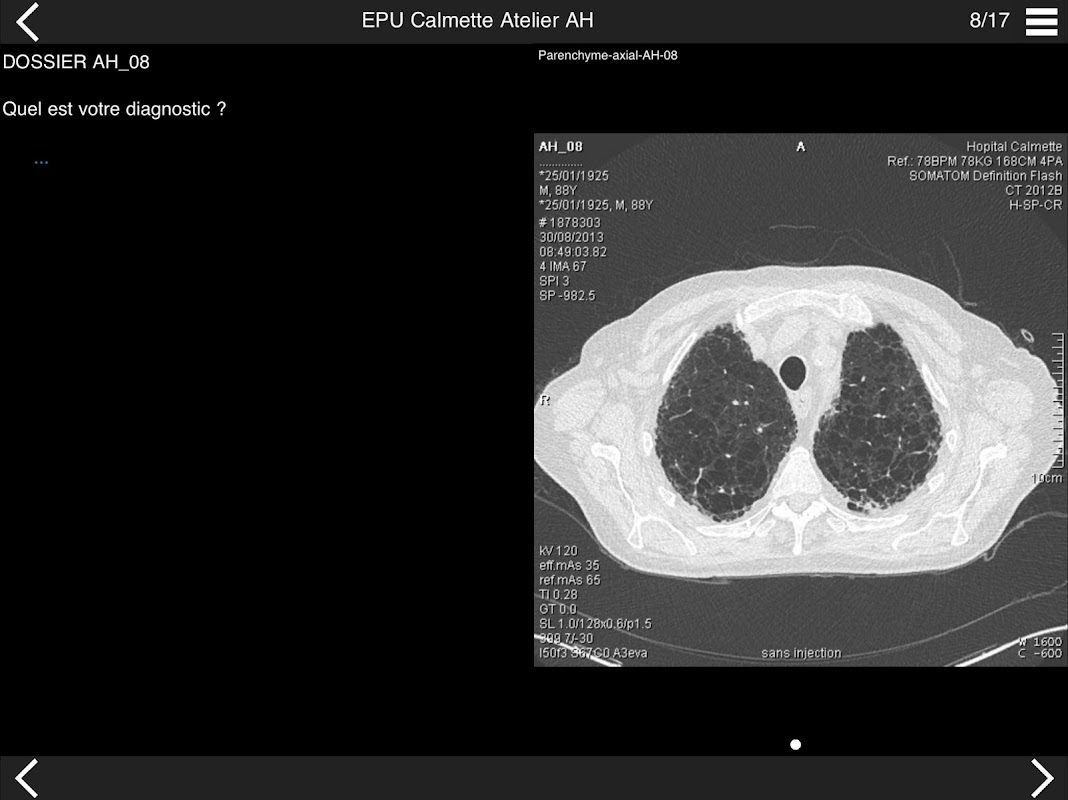

Retrouvez les cas cliniques du Cours intensif de TDM multicoupe du thorax dans cette application.

* Pathologie interstitielle : lésions élémentaires et « patterns »